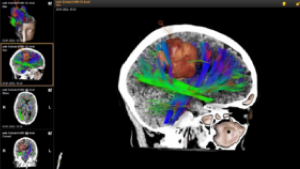

Η κύρια χρήση του είναι αναμφίβολα στην ογκολογία. Στην εικόνα 1 απεικονίζεται ο όγκος του εγκεφάλου με ανοικτό καφέ χρώμα, ενώ επίσης απεικονίζονται διάφορες πολύχρωμες δεσμίδες γύρω του καθώς και μερικές μέσα σε αυτόν, οι οποίες είναι ουσιαστικά νευρικές οδοί που είναι υπεύθυνες για κρίσιμες νευρικές λειτουργίες. Στην ουσία στόχος του χειρουργείου είναι να αφαιρέσουμε τον όγκο χωρίς να τραυματίσουμε τις δεσμίδες.

Ειδικές τεχνικές της μαγνητικής τομογραφίας, όπως η μαγνητική δεσμιδογραφία (DTI, Diffusion Tensor Imaging), μπορούν να ενσωματωθούν στις δομές που απεικονίζει η νευροπλοήγηση. Ο συνδυασμός αυτός αυξάνει σαφέστατα την ασφάλεια του χειρουργείου, αφού πλέον γνωρίζουμε που βρίσκονται οι νευρικές δεσμίδες, δηλ. οι συνδέσεις των νευρικών οδών μέσα στον εγκέφαλο.